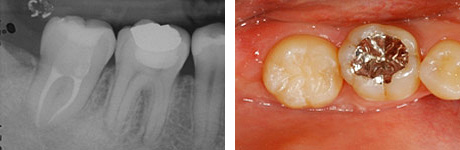

歯根完成歯親知らずの移植

左:治療前のCT画像。

右:治療前の口腔内。

24歳、女性。右下第二大臼歯部(受容側)へ親知らず(ドナー歯)を移植してほしいという希望で来院されました。

ドナー歯はすでに歯根が完成しています。このような場合、移植後に歯髄(神経)の治療が必要です。

左:移植のために抜歯された親知らず(ドナー歯)。

右:移植直後。

左:移植直後のエックス線写真。

右:移植後1ヶ月。